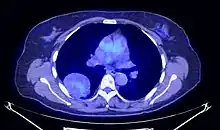

En tomodensitométrie[20],[31], quelle que soit la localisation, une tumeur fibreuse solitaire apparaît comme une masse tissulaire ovoïde ou lobulée, bien délimitée, refoulant les structures voisines sans les envahir. Elle se rehausse fortement après injection de produit de contraste. Les tumeurs de petite taille sont homogènes, mais les plus volumineuses présentent des plages hétérogènes de nécrose et d'hémorragie intra-tumorale. Il n'y a pas habituellement de calcifications et, lorsqu'elles sont présentes, elles sont de petite taille[31]. Les tumeurs malignes peuvent se présenter accompagnées de nodules pulmonaires métastatiques, et tendent à être plus volumineuses et plus hétérogènes[42].